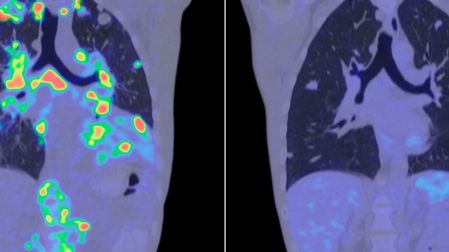

Desde el punto de vista técnico, algunos estudios reconocen que durante una biopsia puede ocurrir un desplazamiento microscópico de células, fenómeno conocido como needle tract seeding.

Sin embargo, una revisión publicada en la revista Cancers aclara que este evento no se traduce, en la gran mayoría de los casos, en recurrencia del cáncer, metástasis a distancia ni disminución de la supervivencia.

La llamada siembra tumoral es un término real en medicina y se refiere a la implantación de células tumorales en el trayecto de un procedimiento médico, como una biopsia o una cirugía mínimamente invasiva. Aunque existe, es un fenómeno poco común.

Un estudio publicado en Frontiers in Oncology analizó más de 8,000 casos reportados en distintas especialidades médicas. Sus conclusiones son claras:

- La siembra tumoral es inusual en comparación con el enorme número de procedimientos que se realizan cada año.

- Se ha descrito con mayor frecuencia en ciertos tipos de biopsias o cirugías laparoscópicas específicas, no en la cirugía abierta convencional.

- La mayoría de los reportes corresponden a carcinomas y adenocarcinomas, lo que no significa que todos los pacientes con estos cánceres estén en riesgo.

Los propios autores subrayan que este fenómeno no cambia el balance entre riesgos y beneficios de los procedimientos diagnósticos y terapéuticos actuales.